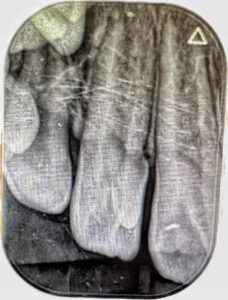

En la inspección radiográfica no se observa la presencia de cuernos pulpares accesorios, la pieza 22 se encuentra en estadio de formación de Nolla #9 (Figura 4).